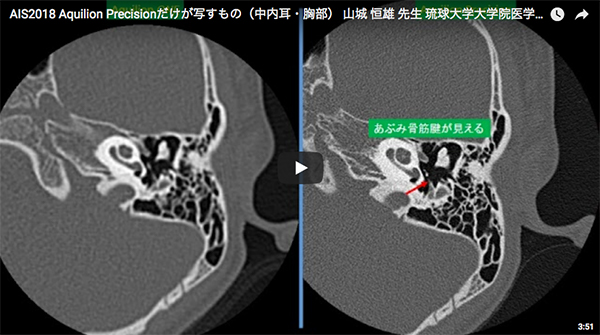

また,これまではほぼ視認できなかったいくつかの構造物も,Aquilion Precisionで視認可能になっている。代表的かつ重要な構造物として,鼓室背側(錐体腔)から起始し,あぶみ骨頸部につながる「あぶみ骨筋腱」がある。あぶみ骨筋(腱)は,鼓膜張筋(腱)とともに耳小骨に停止する重要な筋であるが,従来のCT(コーンビームCT含む)ではほとんど描出できず,これまではその異常に言及することはまず不可能であった。Aquilion Precisionでは,かなりの高確率であぶみ骨筋腱を描出でき(図3),それにより従来は耳鼻科医のみが手術時に確認できたような,あぶみ骨筋腱の異常石灰化などのまれな病態も,術前にCTで診断できるのではと大いに期待している。

図3 Aquilion Precisionで描出されるあぶみ骨筋腱

(0.25mm厚)